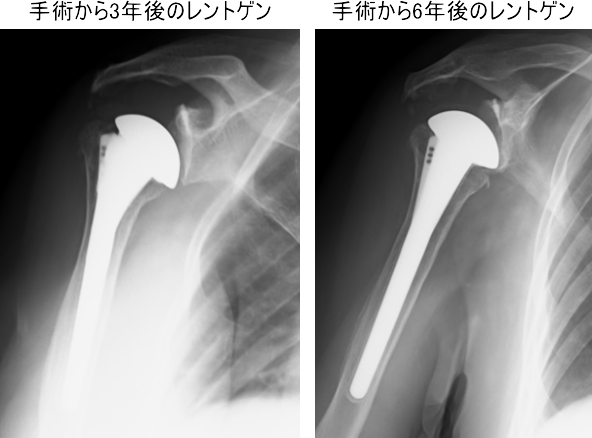

75歳 女性 右肩

以前に変形性肩関節症で人工肩関節置換術を施行しています

CT でよくみると関節窩がすりへっています